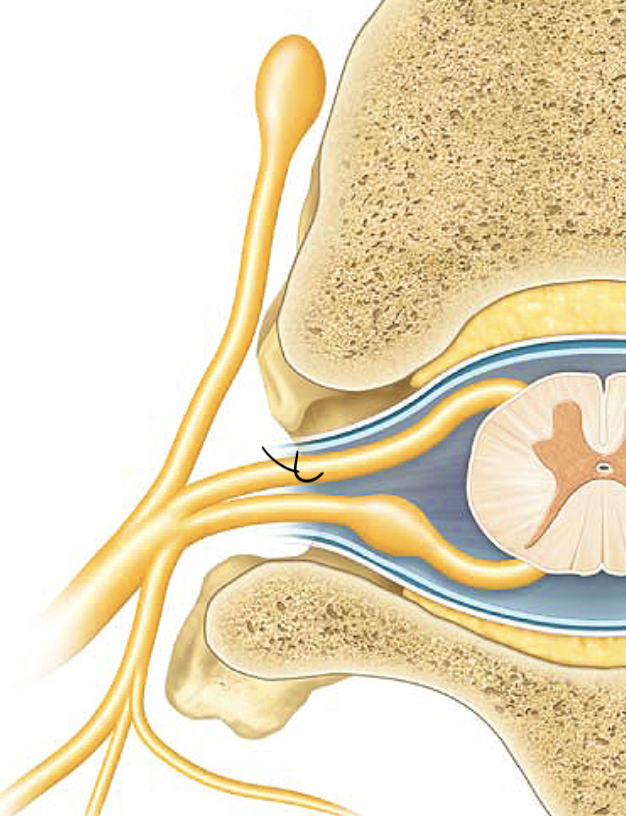

dorsal root

the sensory branch of each spinal nerve

dorsal root ganglion

contains cell bodies of sensory neurons

ventral root

the basal branch of each spinal nerve; carries motor neurons

spinal nerve

a peripheral nerve attached to the spinal cord. Motor and Sensor nerve.

dorsal ramus

the division of posterior spinal nerves that transmit motor impulses to the posterior trunk muscles and relay sensory impulses from the skin of the back

ventral ramus

what. is the second arrow pointing at?